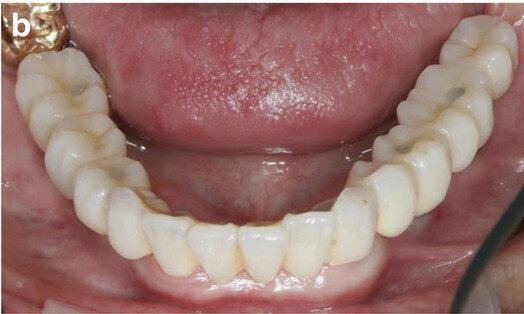

Fig. 9a: Occlusal views of the abutments (a) and of the immediate provisional restoration that were passively bonded in situ (b).

Fig. 9b: Occlusal views of the abutments (a) and of the immediate provisional restoration that were passively bonded in situ (b).

Immediate loading

After removal of the second surgical template, the standard titanium abutments were mounted on to the implants at a torque of 15 Ncm (Fig. 9a). The gaps between the abutments and the FDP were filled with a dual-curing composite material and the screw-retained immediate provisional FDP delivered. The occlusion required only minor adaptations owing to the accurate digital preoperative planning (Fig. 9b). The postoperative panoramic radiograph showed the parallel axes of the six implants (Fig. 10).